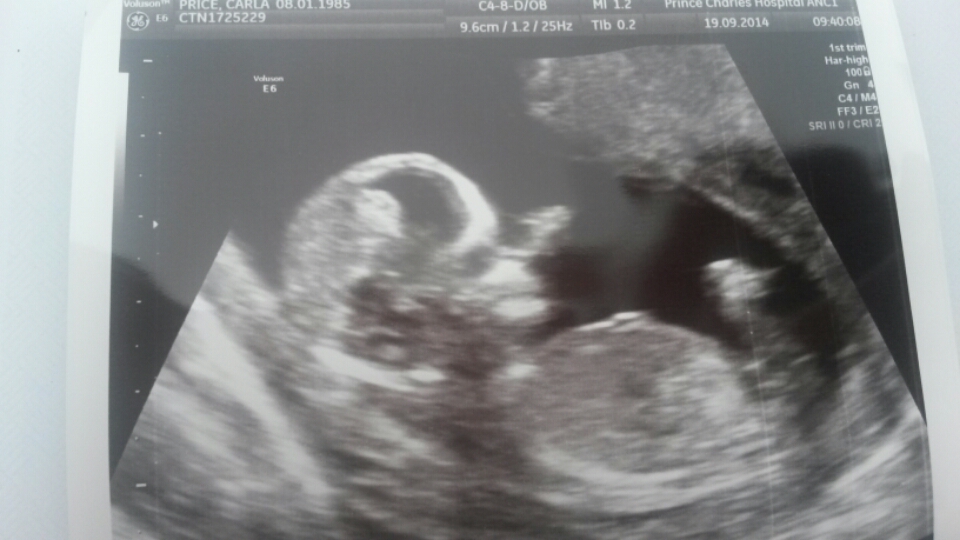

Hi,this is my scan at 13+1, is there a nub showing? Any gender clues?